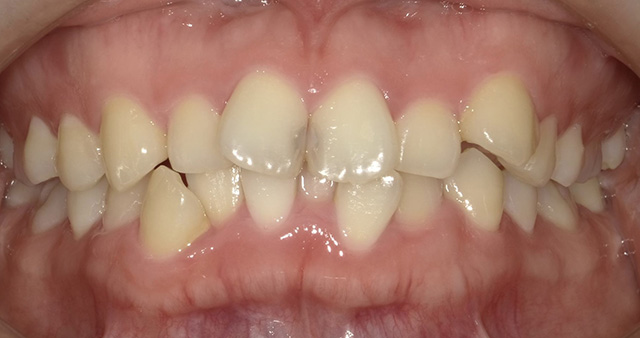

上顎(じょうがく)の糸切り歯(犬歯)が歯並びから飛び出している状態を八重歯(やえば)といい、歯並びが凸凹(でこぼこ)になっている状態を、乱ぐい歯といいます。これらは歯並びが悪い状態を指し、叢生(そうせい)とも呼ばれています。顎(あご)が小さいと歯が生える十分なスペースがないため、歯と歯が重なり合って、叢生が生じると考えられています。叢生は、歯みがきの時に歯ブラシが届きにくく、歯と歯の間に食べかすがたまり、むし歯や歯周病が起こりやすくなります。